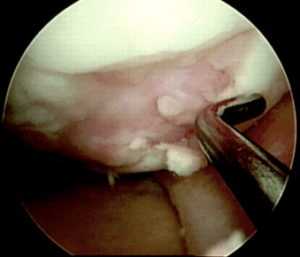

• Травмы циклопа:

о Очаговая фиброзно-синовиальная ткань в передней межмыщелковой вырезке

о На артроскопии определяется «голова» с центральной областью нарушения пигментации; отсюда вытекает название травма циклопа